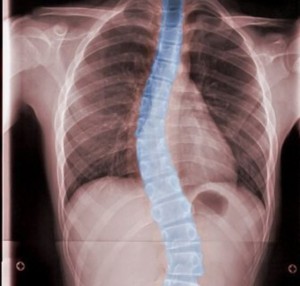

انحراف ستون فقرات و بارداری

اسکولیوز یا انحراف ستون فقرات و بارداری بیشتر از حالتی که فرد به تنهایی دچار یکی از این شرایط باشد، میتواند در صورت بروز همزمان برای فرد نگرانکننده باشد. به هر حال، مهم است توجه داشته باشید به خاطر ابتلای مادر به اسکولیوز، نوزاد در معرض خطر قرار نمیگیرد.